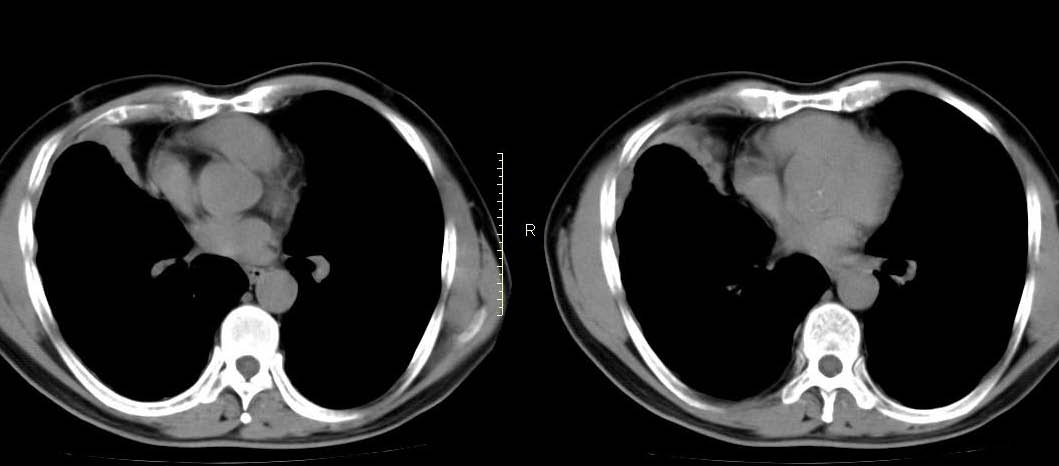

男,56岁,右侧腋窝下巨大软组织包块转移。欢迎讨论。

该病例为已经确诊的右侧恶性胸膜间皮瘤病例,有青石棉接触史,早期就是胸水,右侧胸壁“花边状改变”,心隔角区软组织阴影形成。近期右侧腋窝下巨大软组织包块,病检为转移瘤。图片没有完全考来,主要是给大家看一下胸膜间皮瘤的病例。,右侧

右侧腋窝下巨大软组织包块已经被切除后的ct片,该病例有多家医院较多的ct检查片。

右心膈角区一不规则肿块伴相邻胸膜不规则增厚,考虑胸膜间皮瘤(恶性)?右肺中叶内侧段肺癌?建议穿刺活检。